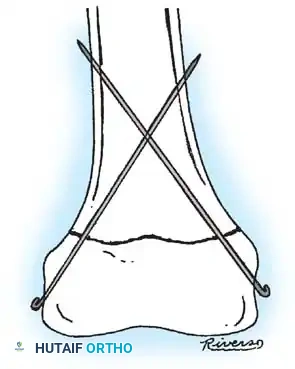

ESIN relies on the principle of symmetric, three-point fixation. Two pre-bent elastic nails are inserted (usually retrograde from the distal femur) and advanced across the fracture site. The restorative forces of the bent elastic nails pushing against the inner cortical walls provide rotational and angular stability while allowing micromotion that stimulates robust secondary bone healing (callus formation).

Biomechanical principles of Elastic Stable Intramedullary Nailing (ESIN), demonstrating the three-point cortical contact required for stability.

Intraoperative fluoroscopy demonstrating the retrograde insertion of elastic nails through the distal femoral metaphysis.

3. Insertion: The nails are pre-bent to an apex that will sit exactly at the fracture site. They are advanced sequentially to the fracture.

4. Reduction and Crossing: The fracture is reduced closed. The nails are advanced across the fracture into the proximal metaphysis. Crucially, the nails must cross above or below the fracture site, never exactly at the fracture level, to maintain stability.

5. Final Seating: The nails are driven into the proximal femoral metaphysis, with the lateral nail terminating near the greater trochanter and the medial nail near the lesser trochanter.

Fluoroscopic view showing the elastic nails crossing in the diaphysis, ensuring symmetric construct rigidity.